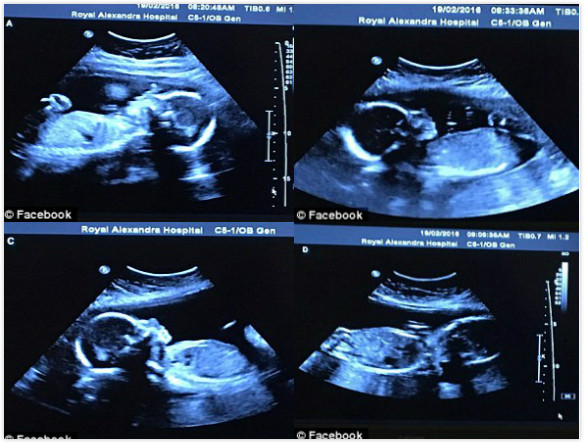

貝莎妮回想起當時去醫院照超音波的情況,「醫生仔細地看著螢幕,接著開始數,一個寶寶、兩個寶寶、三個寶寶…當時我心想,『妳可以停下了,三個寶寶已經夠了。』沒想到她又說出第四個寶寶。」

「我很慶幸當時的自己是躺著的,我從來沒想過肚子裡竟然會有四個寶寶。我以為自己聽錯了…我老公則是差點暈過去,他甚至必須坐下來才有辦法恢復。」